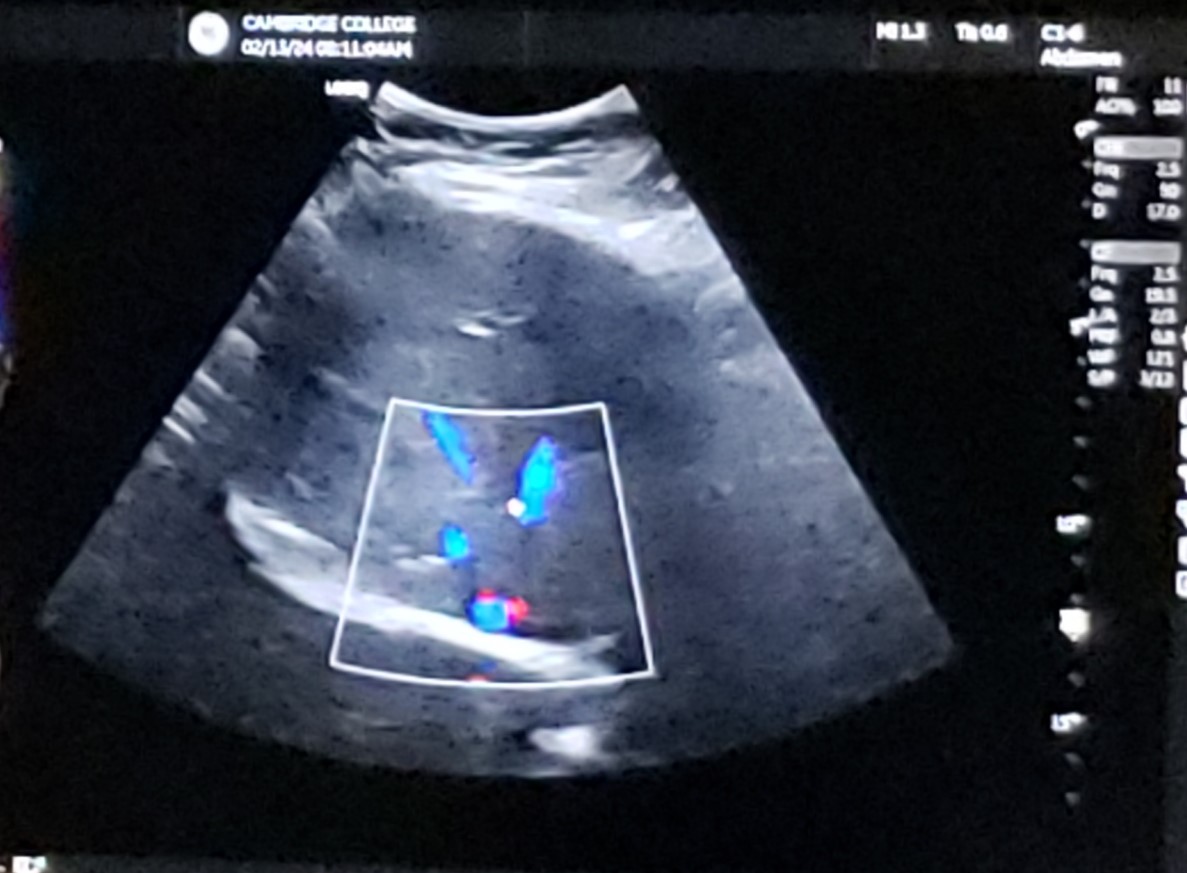

Trans RLL w/ MPV - color

15